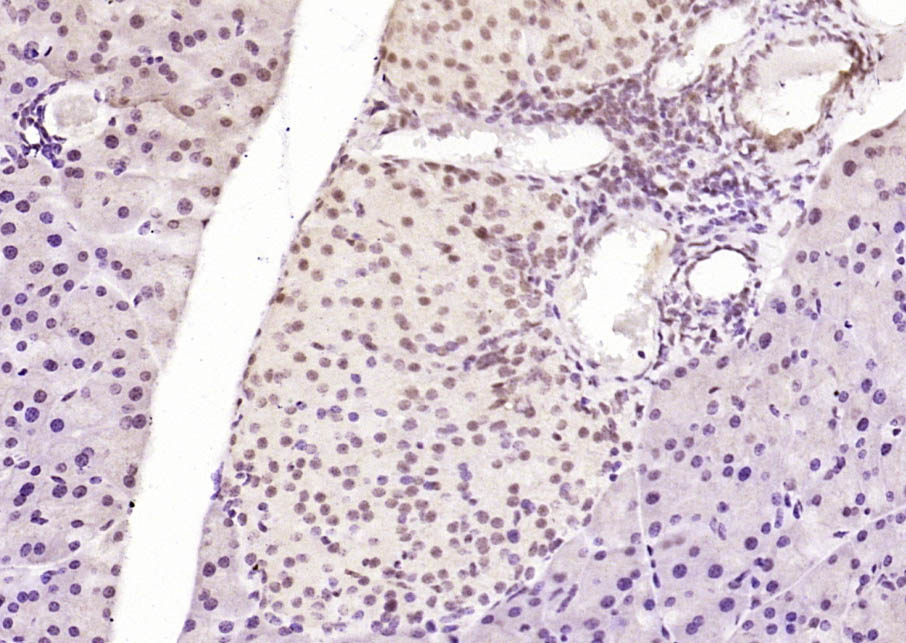

| IHC-P | Human, Mouse | Rat | 1:100-500 |